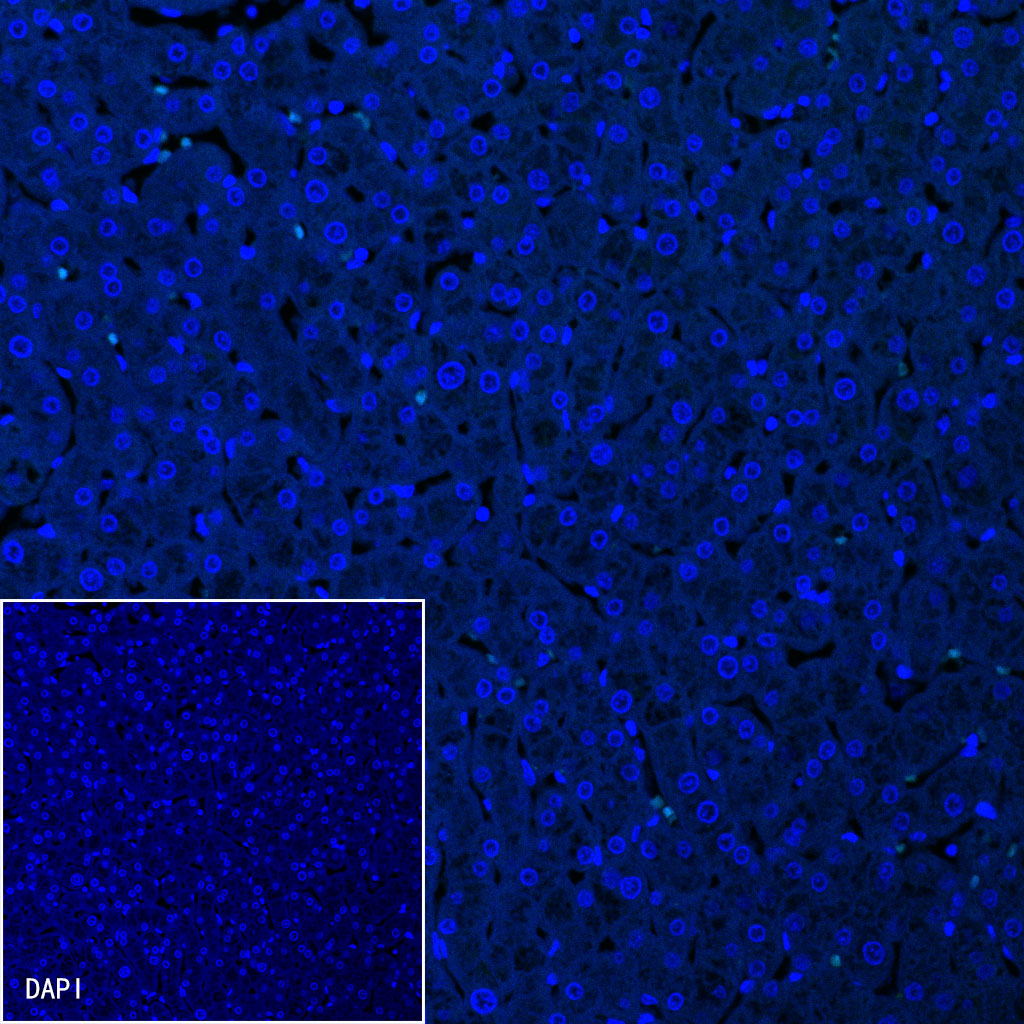

Immunofluorescence

Negative control: IF shows negative staining in paraffin-embedded human liver. Anti-Somatostatin antibody was used at 1/250 dilution (Green) and incubated overnight at 4°C. Goat polyclonal Antibody to Rabbit IgG - H&L (Alexa Fluor® 488) was used as secondary antibody at 1/1000 dilution. Counterstained with DAPI (Blue). Heat mediated antigen retrieval with EDTA buffer pH9.0 was performed before commencing with IF staining protocol.